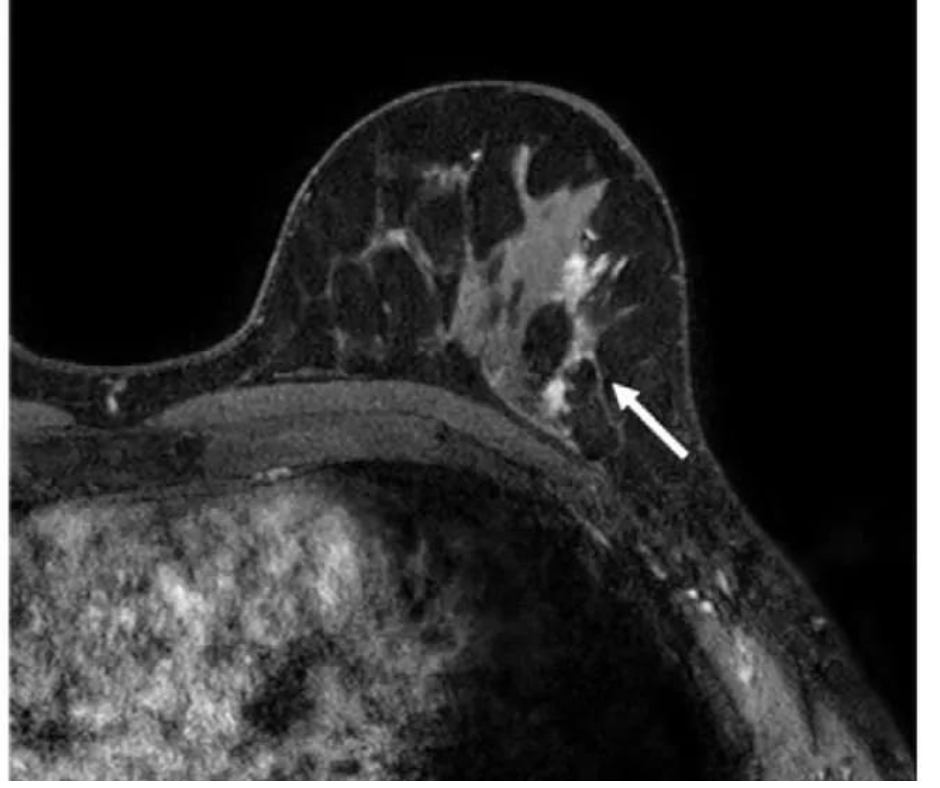

In a new literature review, researchers noted key findings on the use of breast MRI in facilitating breast cancer detection for women with dense breasts and others at high-risk for breast cancer.

In a study of nearly 2,500 women with BRCA1 or BRCA2 sequence variations, researchers found that MRI surveillance led to a 3.2 percent breast cancer mortality risk at 20 years in contrast to a 14.9 percent mortality risk for those who did not have MRI surveillance.